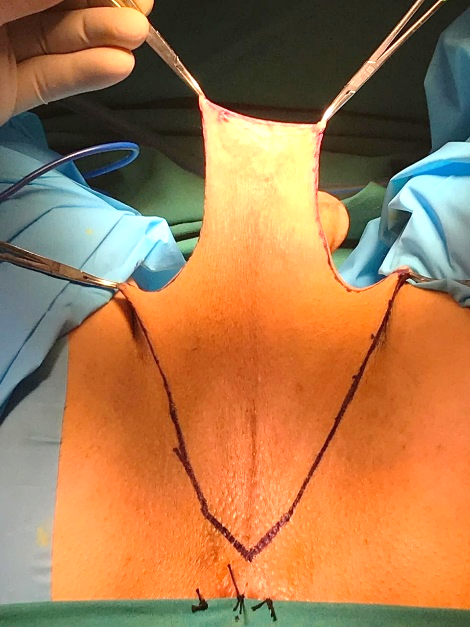

En la técnica desarrollada por Dr. Guillermo Mac Millan, se utiliza un colgajo perineal de irrigación inferior además del escroto tratado como injerto libre (Figura 4). Otra alternativa para recubrir el canal vaginal, especialmente en cirugías de revisión y/o en personas trans que, producto de un bloqueo hormonal precoz presenten mínimo desarrollo de estructuras genitales masculinas, es el uso de algún segmento intestinal, principalmente colon sigmoides. Las ventajas de este último es el aspecto mucoso, la lubricación y la posibilidad de alcanzar mayor profundidad. Las desventajas son posible secreción de mal olor y el riesgo propio de una anastomosis intestinal.

El post operatorio de la cirugía genital femenizante requiere un estricto régimen de dilataciones diarias de la neo vagina, así como un control médico cercano para el diagnóstico y eventual tratamiento de las posibles complicaciones, que ocurren en un 15% de los casos aproximadamente(7). Las más frecuentes son dehiscencia de herida operatoria, formación de tejido granulatorio, sangrado, estenosis neo vaginal, dolor prolongado, vellos en la neo vagina y deficientes resultados estéticos. Las complicaciones más temidas ocurren en menos del 1% y son fístulas recto-neo vaginales o uretro-neo vaginales. Las tasas de satisfacción post operatoria, tanto estética como funcional, superan el 80% (Figura 5).